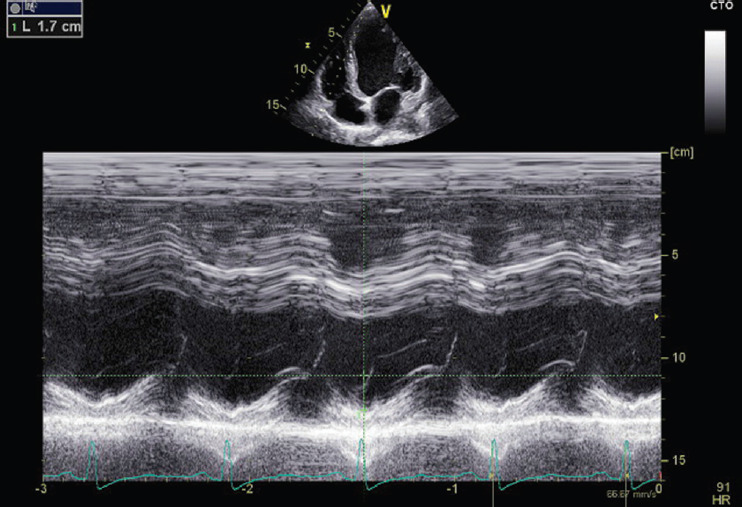

Peripartum cardiomyopathy (PPCM) is a specific form of cardiomyopathy that manifests toward the end of pregnancy or within 5 months postpartum, characterized by a decrease in cardiac output due to impaired myocardial function. This condition has a multifactorial origin, influenced by genetic predispositions, inflammatory processes, autoimmunity, hormonal variations, and nutritional deficiencies. Prognosis varies among patients: while some recover completely within 6 months, others may develop chronic cardiac dysfunction requiring long-term treatment. Vericiguat, a soluble guanylate cyclase stimulator, has shown promising results in the treatment of heart failure with reduced ejection fraction. This drug works by enhancing the nitric oxide signaling pathway, promoting vasodilation, and improving myocardial function. Although the use of vericiguat in PPCM is not yet fully documented, its potential benefits suggest that it may represent a valid therapeutic option when standard therapies are insufficient for symptom control. We present the case of a 32-year-old woman with PPCM, initially undiagnosed, who developed severe symptoms of dyspnea, orthopnea, and peripheral edema postpartum. These symptoms were accompanied by a significant reduction in left ventricular ejection fraction. Following a suboptimal response to standard heart failure therapy, vericiguat was incorporated into her treatment regimen. In subsequent outpatient follow-ups, the patient's symptoms progressively improved, and left ventricular systolic function markedly increased. The patient became asymptomatic and was able to resume her normal daily activities. While this case suggests that vericiguat could be an effective adjunctive treatment for PPCM, it remains unclear whether these improvements were directly attributable to vericiguat or could have occurred with continued standard therapy alone. Further studies are needed to define the role of vericiguat in this condition.

Abstract Image